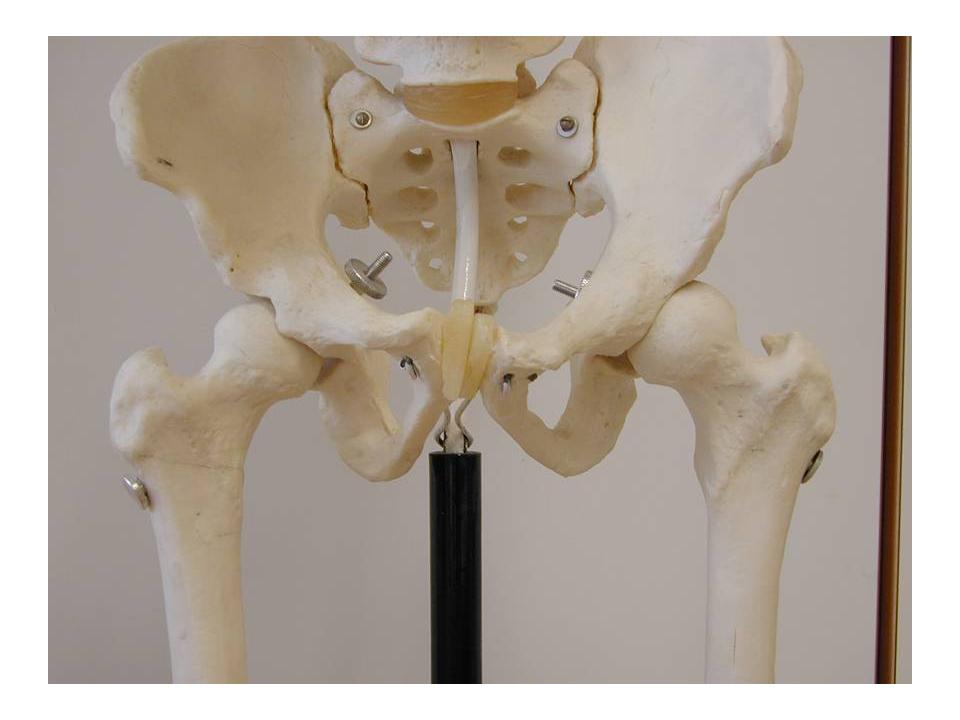

Das Hüftgelenk verbindet den Oberschenkelknochen mit dem Becken. Es handelt sich dabei um ein Kugelgelenk. Das heisst, dass der Kopf des Oberschenkelknochens kugelförmig gestaltet ist und in einer passgenauen Hüftpfanne im Becken sitzt.

Ein Kugelgelenk ermöglicht einen sehr grossen Bewegungsumfang in allen Richtungen. Für viele Alltagsaktivitäten ist eine gute Hüftbeweglichkeit unabdingbar. Bewegungseinschränkungen führen somit zu erheblichen Funktionseinbussen.